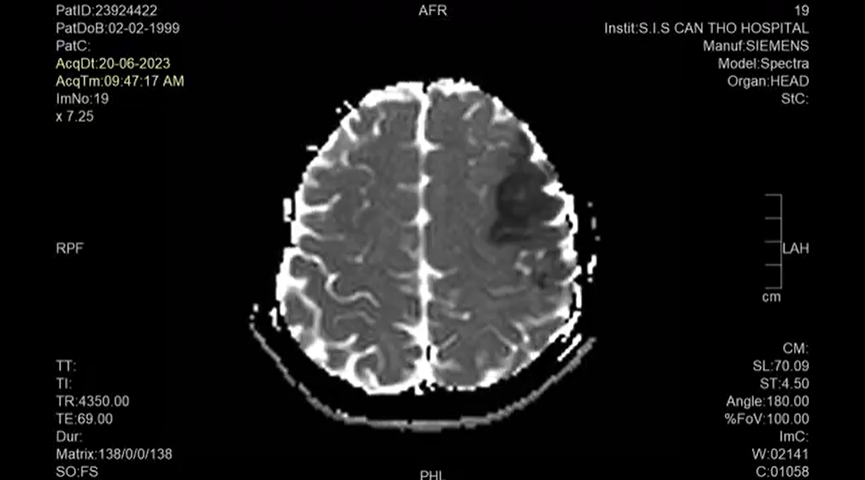

Theo TS.BS Trần Chí Cường, đây là trường hợp còn rất trẻ, nhập viện trong tình trạng yếu nửa người bên phải, triệu chứng điển hình là nói khó. Sau khi chẩn đoán hình ảnh cho thấy bệnh nhân có nhồi máu não thái dương trái thuộc vùng cấp máu của động mạch não giữa bên trái, có tổn thương trung tâm ngôn ngữ. Đó là lý do bệnh nhân này không thể nói được và mất khả năng ngôn ngữ (mất ngôn ngữ Broca).

Hình ảnh MRI não của bệnh nhân (ảnh: BVCC)

Trong trường hợp này, bệnh nhân sẽ không thể trả lời hoặc diễn đạt bằng ngôn ngữ khi nghe lời nói từ những người xung quanh. Sau khi điều trị tại Bệnh viện Đa khoa Quốc tế S.I.S Cần Thơ khoảng 2 tuần, người bệnh đã bắt đầu hiểu và phát âm được một số từ và trả lời bác sĩ bằng chữ viết. Đây là dấu hiệu may mắn trong vấn đề phục hồi.